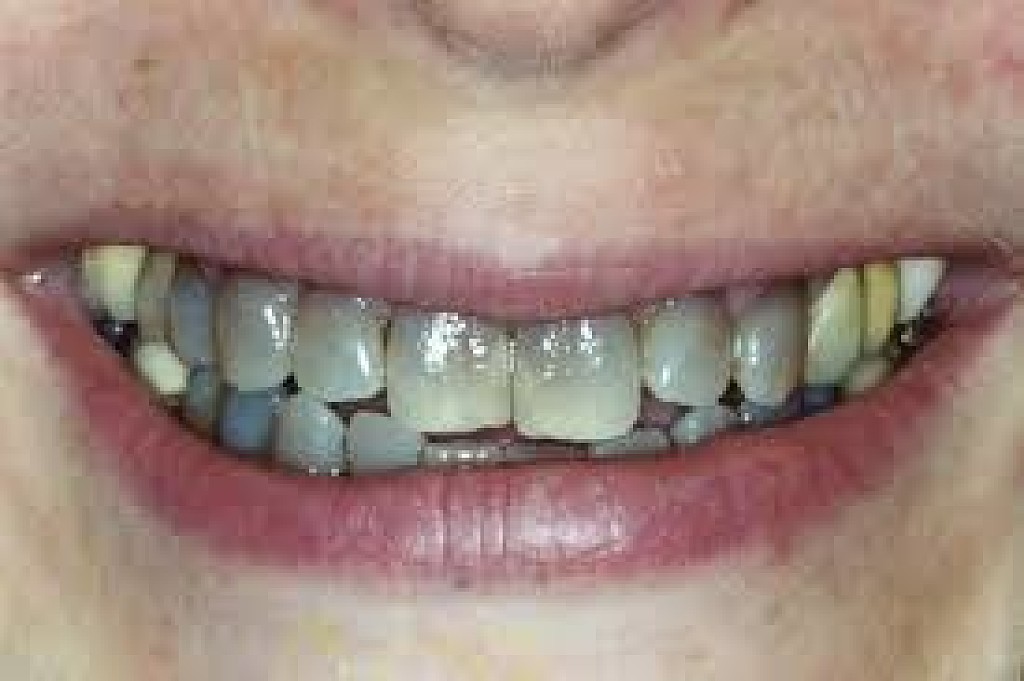

Black Teeth: Symptoms, Causes and Treatment

Black teeth can be a concern for many people; a black tooth will affect your smile and impact on your confidence. If you have a black tooth, read on to find out more about the symptoms and causes and treatments that may be available.

What causes a tooth to go black?

There are many reasons why a tooth can begin to go black, anything from simple staining to the death of the tooth can cause blackness and darkening.

Poor oral hygiene

Poor oral hygiene can cause your tooth to go black. In the early stages this is likely to be staining from substances like tobacco, red wine and strongly colored food. If your oral hygiene routine is not thorough enough to remove the acid-excreting bacteria each day, the acid will slowly eat away at your tooth.

As the tooth gets eaten away, tooth decay sets in. Tooth decay naturally looks black and can give the appearance of a black tooth. This gives the look of rotten teeth and is a classic result of not looking after your teeth for a considerable period of time.

The death of a tooth

When a tooth dies, the blood supply – which gives the tooth its natural, healthy color – will stop. Because the tooth is not receiving the nutrients it needs, it will begin to necrotise, darken, die and slowly go black.

Will my tooth go black after root canal?

A common misconception is that a tooth will go black after a root canal treatment. Teeth will often go black before root canal treatment as the tooth rots and decomposes on the inside. If root canal treatment is done well, all of the decomposing tissue will be removed and the blackness will not get worse. There may, however, be some mild darkening of the tooth after a root canal, depending on exactly how the root canal treatment is done and with which material.

How long does it take for a tooth to go black?

If the cause of the blackness is due to tooth decay, the blackness can happen over a period of years. If the cause of the blackness is due to trauma, as soon as the blood supply has been cut off from the tooth, the internal tooth tissue will begin to die and turn black.

Will a dead tooth go black?

If a dead tooth is left untreated, it will go black as the internal tooth tissue dies and decomposes. If the dead tooth has been root treated with a tooth-colored treatment, the tooth may not go completely black, although it may darken slightly.